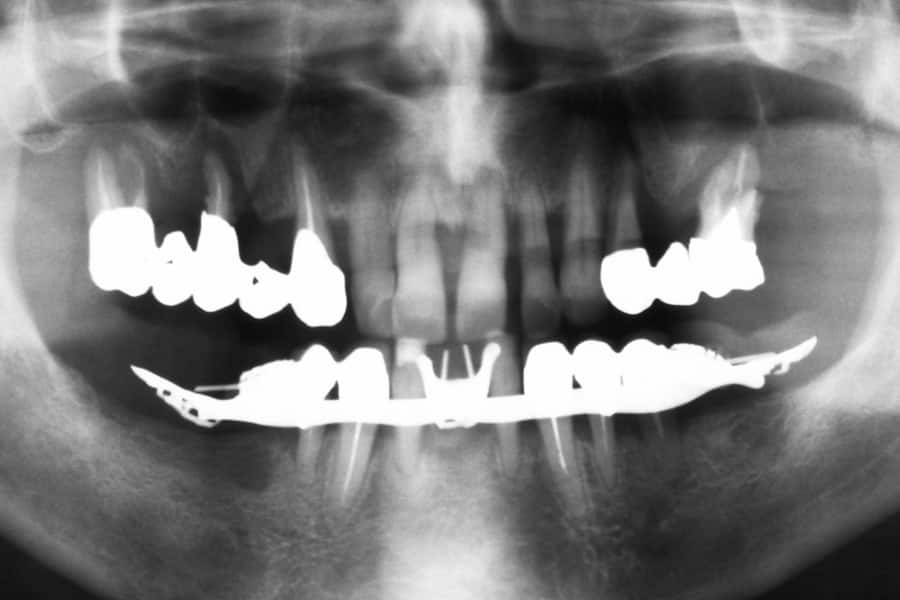

Guardando la prima radiografia panoramica, sembrava che Marco non avesse abbastanza osso nella parte superiore destra per inserire gli impianti. La malattia parodontale aveva infatti consumato molto tessuto osseo nella zona dei premolari.

Normalmente, per risolvere questo problema e posizionare gli impianti, si ricorre a un intervento chiamato rialzo del seno mascellare, che consiste nell’aggiungere osso nella mascella. Per evitare a Marco questa procedura invasiva, ci siamo affidati all’implantologia dinamica.

Abbiamo eseguito una TAC e, grazie a un software avanzato, abbiamo creato un modello 3D del suo cranio. Questa tecnologia ci ha permesso di scovare una zona di osso nascosta, situata dietro il seno mascellare, di ottima qualità e perfetta per accogliere un impianto. Questa porzione di osso era completamente invisibile dalla semplice radiografia tradizionale.